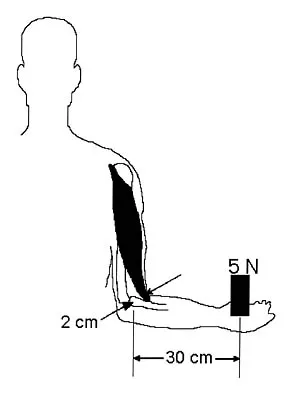

The acceleration of an object under the influence of a force depends directly on the mass of the object. The angular acceleration of an object under the influence of a moment depends directly on the

Explanation